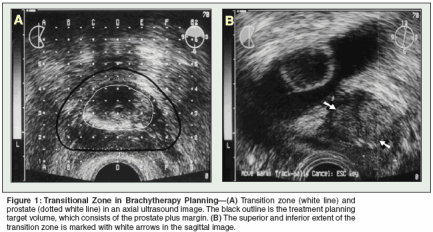

Transition Zone

In contrast to overall prostate size, transition zone volume has consistently correlated with brachytherapy-related urinary morbidity (Figure 1).[20-22] Thomas and colleagues reported that transition zone volume was the most important predictor of acute urinary retention following magnetic resonance-guided prostate brachytherapy.[20] In addition, the transition zone index (TZI = transition zone volume/ prostate gland volume) was reported to correlate with time to normalization of International Prostate Symptom Score (IPSS), maximum increase in IPSS, and the need for postimplant surgical intervention.[21] In patients receiving neoadjuvant hormonal therapy for cytoreduction, IPSS normalization, prolonged catheter dependency, and the need for a postbrachytherapy transurethral resection (TURP) were best predicted by the percent decrease in transition zone volume.[22] Indeed, the transition zone and its variants may have greater predictive power for prolonged urinary dysfunction and the need for subsequent intervention than any other single parameter.